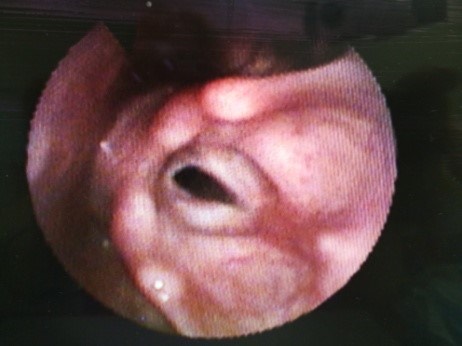

1071. Предположительным диагнозом является